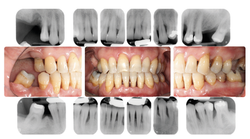

Status Parodontale